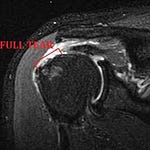

At half a million performed each year in the U.S., rotator cuff surgery is among the most common orthopedic procedures. Which is curious, because the handful of randomized trials testing it have repeatedly found little or no difference between surgery and physical therapy. Even within orthopedics there is deep skepticism, and sham-controlled trials of the procedure are currently underway.1

Meanwhile, as I discussed last week, in a recent MRI study of healthy Finnish people age 40 and over, fixable ‘injuries’ were seen in perfectly functional shoulders. And not just some of them: 96% of people with no shoulder complaints had potentially surgical lesions. Tendon tears, present in 80% of study participants in Kennedy’s age group, appear to be little more than a normal sign of aging. Like wrinkles in the rotator cuff.

In stark contrast, red flags in the data on rotator cuff surgery are big time: namely, the surgery didn’t work—there was no benefit. That ain’t a nit-pick.

Yet now, when Kennedy became a patient, the calculus appears different. Faced with shoulder pain and an expert’s recommendation, he did not turn his own famously cutting eye on the data. Which may be a serious mistake. For a 72-year old man the risks associated with surgery (heart attack, stroke, pneumonia, blood clots, death) are greater than any benefit found in a trial of rotator cuff surgery. And in light of the Finnish data, the notion that whatever MRI finding his surgeon is targeting is the true cause of his shoulder problems is, at best, highly suspect.